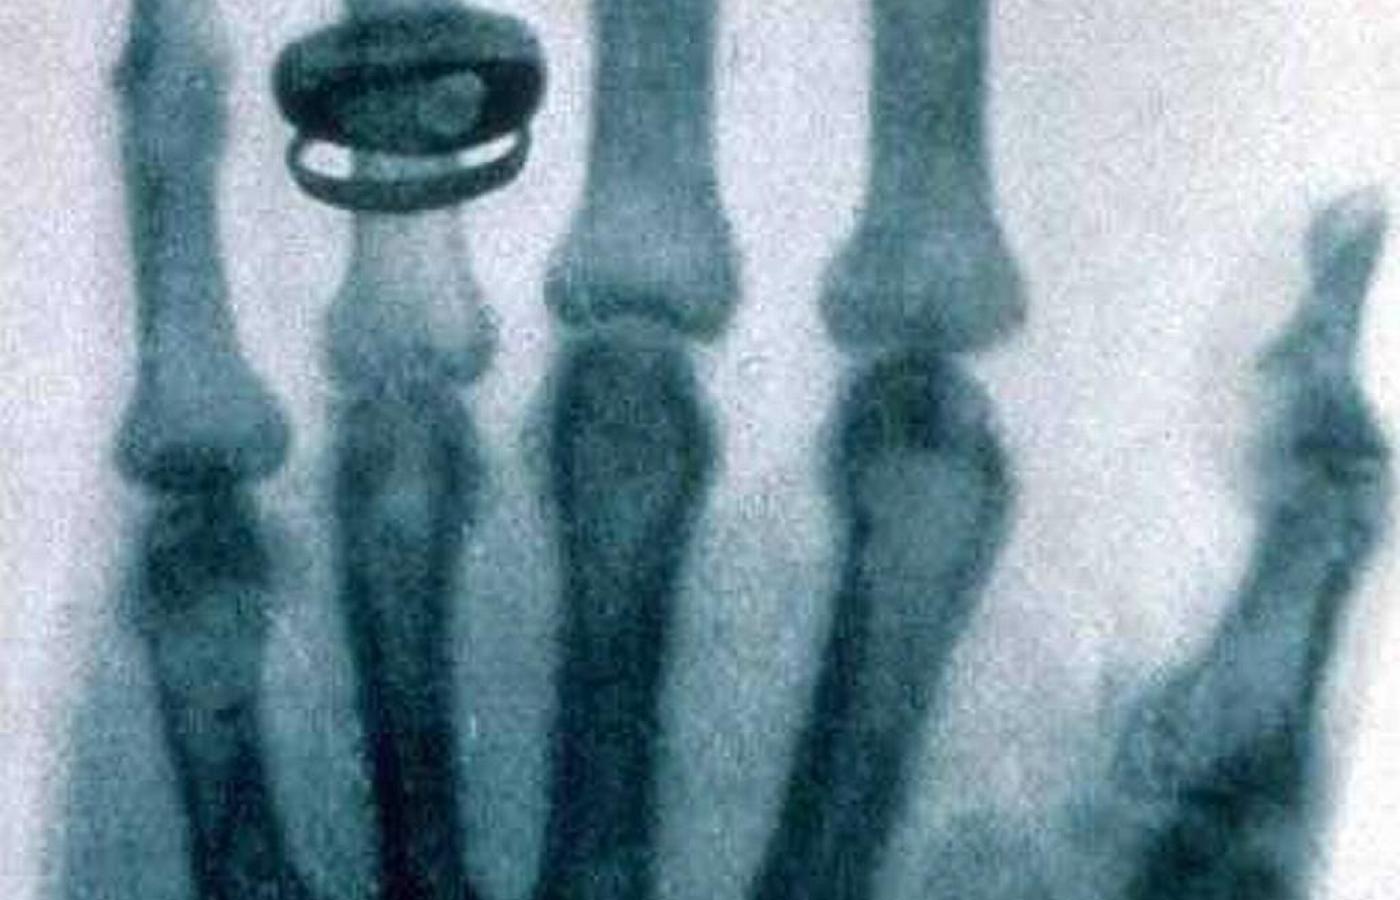

Zdjęcie rentgenowskie dłoni Rudolfa Kollikera wykonane przez Roentgena na posiedzeniu Physical Medical Society w Würzburgu 23 stycznia 1896.Wilhelm Conrad Roentgen/Wikipedia Zdjęcie rentgenowskie dłoni Rudolfa Kollikera wykonane przez Roentgena na posiedzeniu Physical Medical Society w Würzburgu 23 stycznia 1896.